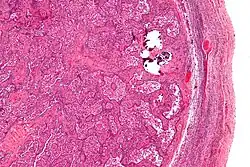

Gonadoblastomas are precancerous lesions that predominantly form in intersex people with gonadal dysgenesis and a Y chromosome.[42][43] This includes conditions such as Swyer syndrome or Turner syndrome with Y chromosome mosaicism.[44][42] These cancer risks are addressed using genetic screening and performing a gonadectomy if necessary.[42]